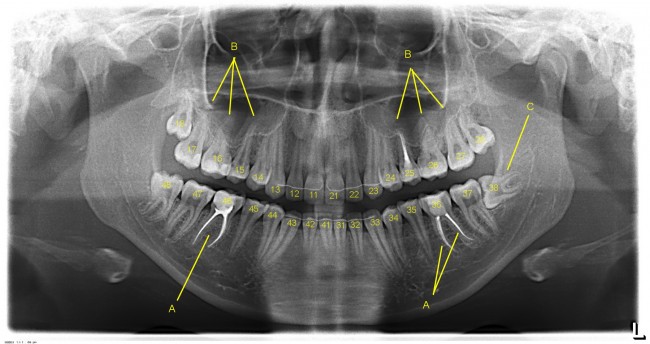

В современной стоматологии используется цифровое обозначение зубов. Вот так, как на расшифровке ортопантомограммы:

На стрелки не обращайте внимания, картинку взял из другой статьи.